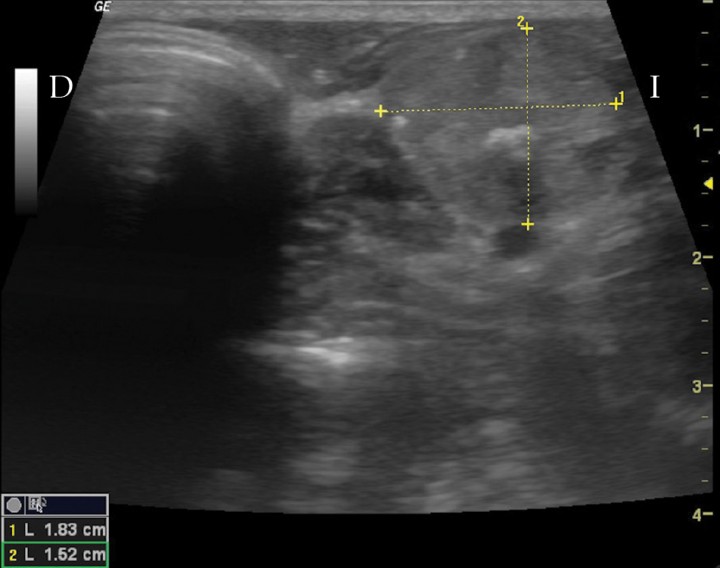

Se ingresó en cuidados intensivos para el tratamiento con fluidoterapia (Ringer Lactato + 5 % de glucosa). Unas 12 h después, se encontraba ya hidratado y nuevamente con hiperglucemia (231 mg/dl), por lo que se instauró el tratamiento con una dosis baja de insulina (Caninsulin®, MSD, Salamanca, España) de 0,2 UI/kg/12 h. Transcurridas 4 horas después de la administración de esta dosis, se observó un nadir de glucosa de 36 mg/dl. La glucosa ascendió a 77 mg/dl a las 6 horas, y a 164 mg/dl a las 9 horas. Transcurridas 12 horas después de dicha administración, la glucosa presentaba un valor de 245 mg/dl. En este momento, debido a la hipoglucemia observada durante el nadir de glucosa, se disminuyó la dosis de insulina a 0,1 UI/kg. El siguiente valor de la glucosa preinsulina fue de 286 mg/dl y, esta vez, el nadir de glucosa a las 4 h fue de 244 mg/dl y el siguiente valor de la glucosa preinsulina, de 291 mg/dl. El paciente recibió el alta y se continuó en casa con este tratamiento de insulina, si bien, dos días después de haber estado hospitalizado, acudió a revisión y persistían la taquicardia (150 lpm) y la taquipnea. Se detectó una hiperglucemia de 470 mg/dl, por lo que se incrementó la dosis de insulina a 0,2 UI/kg/12 h y se realizaron estudios adicionales. La ecografía cervical confirmó la presencia de una masa tiroidea con un diámetro máximo de 1,8 cm (Fig. 3). Se realizó también una punción ecoguiada de la masa y los resultados de la citología indicaron un epitelio tiroideo morfológicamente normal. En las radiografías de tórax y abdomen no se observaron lesiones radiológicas compatibles con metástasis pulmonares o masas.

<p>Imagen ecográfica en plano transversal de la masa cervical. D: derecha. I: izquierda.</p>

Figura 3

Imagen ecográfica en plano transversal de la masa cervical. D: derecha. I: izquierda.